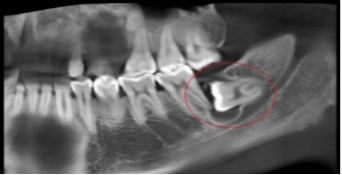

阻生牙(impacted teeth)是指部分萌出或完全不能萌出,且以后也不会自行萌出的牙。好发部位为下颌第三磨牙、上颌第三磨牙及上颌尖牙,其中阻生第三磨牙也叫做阻生智齿。

5、邻牙及支持组织的吸收:当阻生的智齿萌出过程中受阻于第二磨牙时,会引发第二磨牙牙根牙根逐渐吸收,严重者可使下颌第二磨牙远中牙根完全吸收,致第二磨牙松动、疼痛,常常食物嵌塞发生慢性牙周炎,也会造成牙槽骨的炎症性吸收,使第二磨牙反复肿痛。

7、智齿周围囊性病变:下颌阻生的智齿常常形成囊肿,引起骨头吸收。